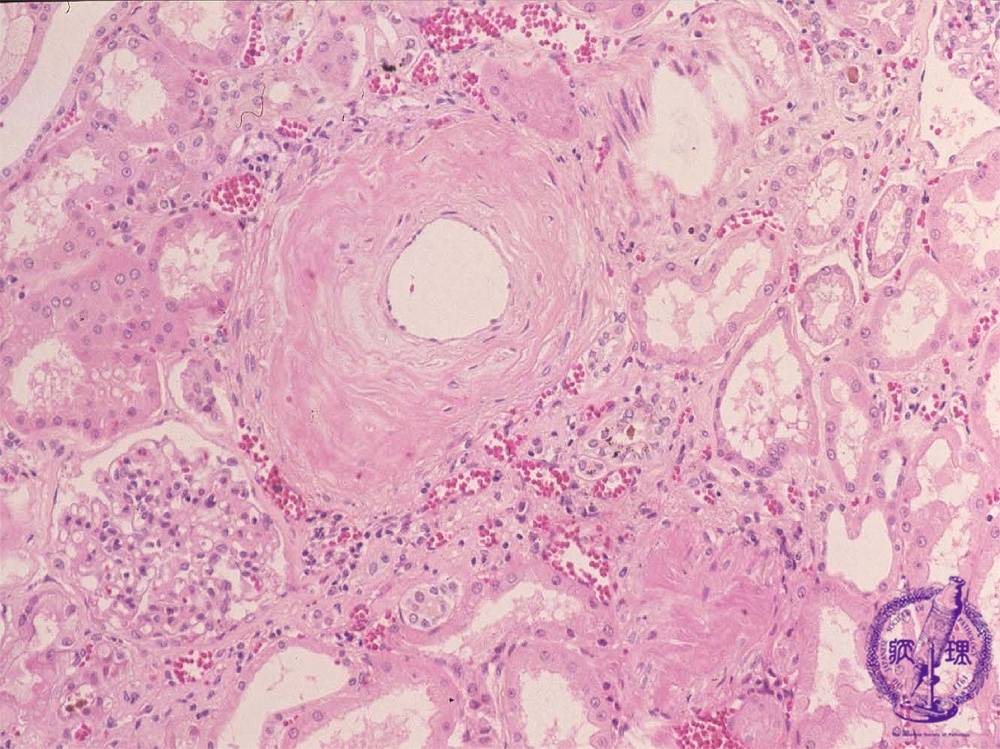

- ★(10)Nephrosclerosis(benign nephrosclerosis)

Microscopic findings (HE, middle power view):Interlobular arterial walls showed thickening and sclerosis (yellow dotted lines, red arrow).